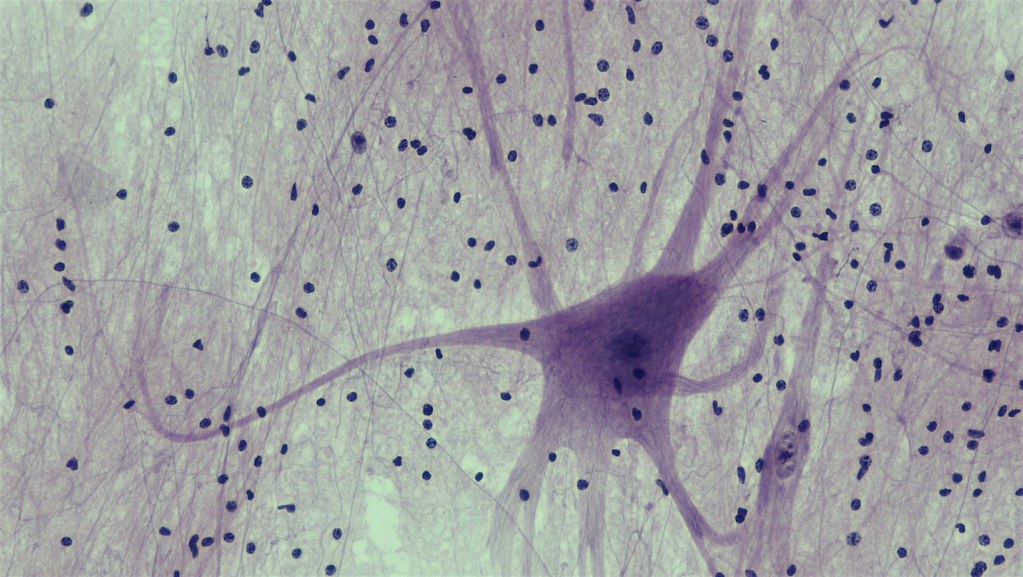

neuron

Ilustrační foto.

Zdroj: Flickr